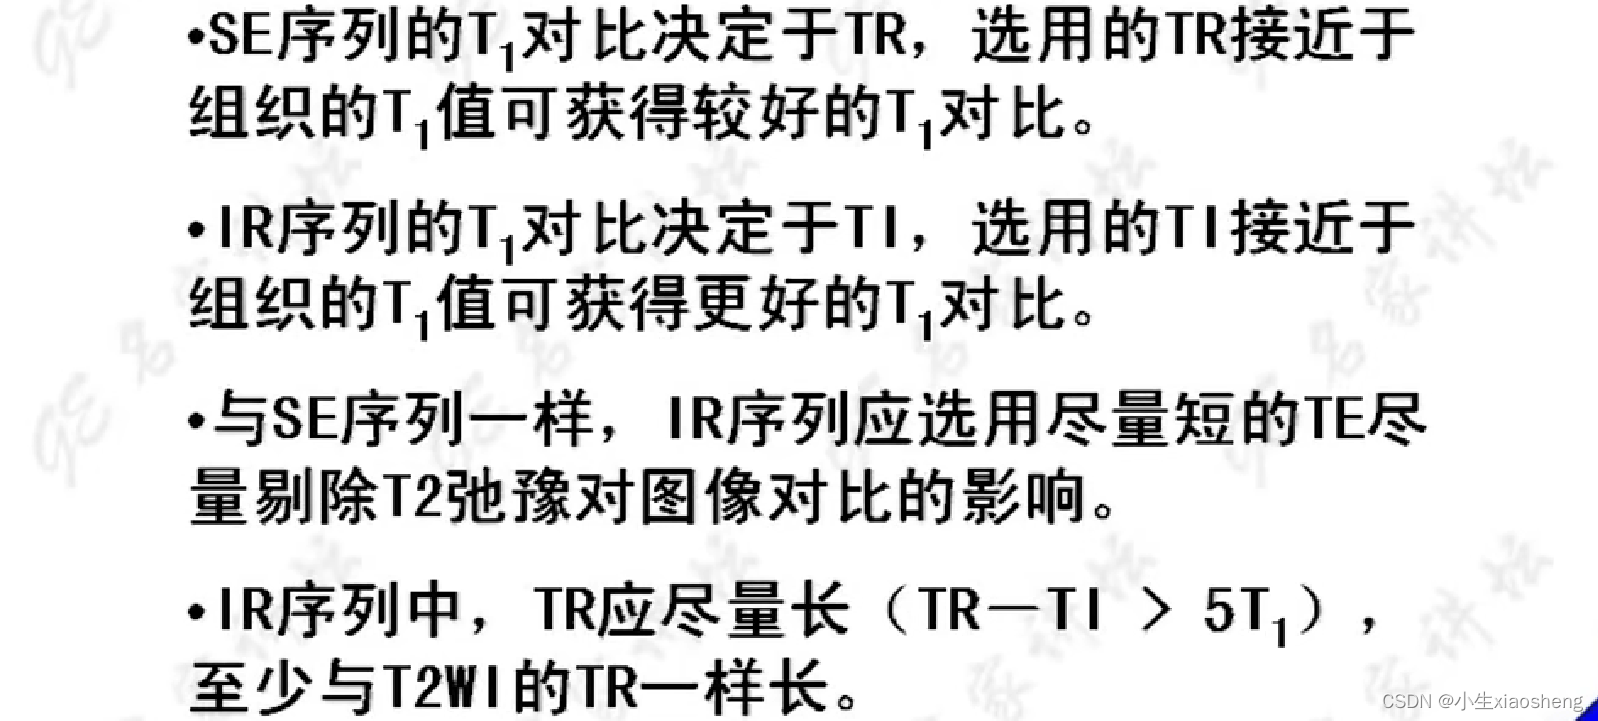

选择合适长的TE获得最好的T2对比:一般TE选择两种组织生物T2值附近可获得最好的T2对比。

选择合适短的TR获得最好的T1对比:一般TR选择两种组织生物T1值附近可获得最好的T1对比。

说明时间越长对应的差距也就越大,说明其结果对比好,更容易看出图片。其中TI为反转时间

2.快速反转恢复序列

通过抑制那么在检查的时候就能针对性检查某种组织信号。几种应用我也不想看了😵